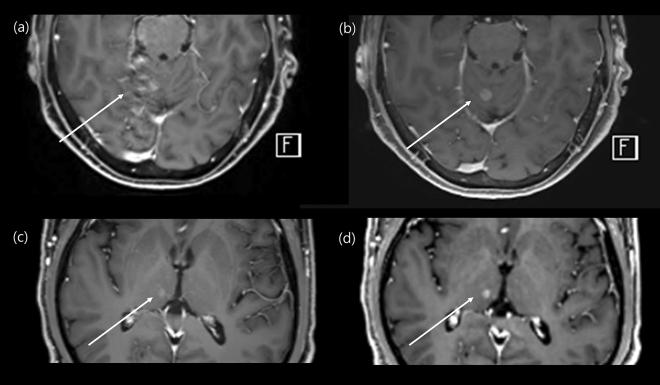

Our objective was to evaluate and compare the diagnostic performance of post-contrast 3D compressed-sensing volume-interpolated breath-hold examination (CS-VIBE) and 3D T1 magnetization-prepared rapid-acquisition gradient-echo (MPRAGE) in detecting intracranial metastasis. Additionally, we analyzed and compared the image quality between the two. We enrolled 164 cancer patients who underwent contrast-enhanced brain MRI. Two neuroradiologists independently reviewed all the images. The signal-to-noise ratio (SNR), contrast-to noise ratio (CNR) were compared between two sequences. For patients with intracranial metastasis, we measured enhancement degree and CNR of the lesion. The overall image quality, motion artifact, gray-white matter discrimination and enhancing lesion conspicuity were analyzed. Both MPRAGE and CS-VIBE showed similar performance in diagnosing intracranial metastasis. Overall image quality of CS-VIBE was better with less motion artifact; however conventional MPRAGE was superior in enhancing lesion conspicuity. Overall, the SNR and CNR of conventional MPRAGE were higher than those of CS-VIBE. For 30 enhancing intracranial metastatic lesions, MPRAGE showed a lower CNR (p = 0.02) and contrast ratio (p = 0.03). MPRAGE and CS-VIBE were preferred in 11.6 and 13.4% of cases, respectively. In comparison with conventional MPRAGE, CS-VIBE achieved comparable image quality and visualization, with the scan time being half of that of MPRAGE.

我们的目的是评估和比较对比增强后 3D 压缩感知容积内插屏气检查(CS-VIBE)和 3D T1 磁化准备快速获取梯度回波(MPRAGE)在检测颅内转移中的诊断性能。此外,我们还分析和比较了这两种方法的图像质量。我们纳入了 164 例接受增强脑 MRI 的癌症患者。两名神经放射科医生独立审查了所有图像。比较了两种序列的信噪比(SNR)和对比噪声比(CNR)。对于有颅内转移的患者,我们测量了病变的增强程度和 CNR。分析了整体图像质量、运动伪影、灰-白质分辨力和增强病变的显著度。MPRAGE 和 CS-VIBE 在诊断颅内转移方面均具有相似的性能。CS-VIBE 的整体图像质量更好,运动伪影更少;然而,常规 MPRAGE 在增强病变的显著度方面更优。总体而言,常规 MPRAGE 的 SNR 和 CNR 均高于 CS-VIBE。对于 30 个增强的颅内转移病变,MPRAGE 显示出较低的 CNR(p=0.02)和对比比(p=0.03)。MPRAGE 和 CS-VIBE 分别在 11.6%和 13.4%的病例中更受青睐。与常规 MPRAGE 相比,CS-VIBE 实现了可比的图像质量和可视化效果,扫描时间仅为 MPRAGE 的一半。